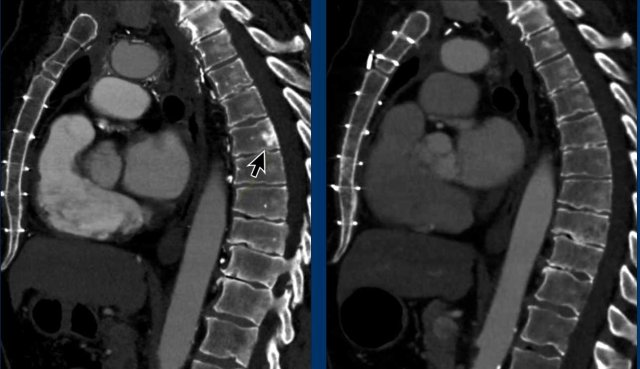

Neuroendocrine tumor of the thymus

Case

These images are of a 36 year-old male with Cushing syndrome, who had a resection of a pituitary adenoma.

The Cushing however persisted and a mediastinal mass was detected.

Images

Solid mass with central calcifications (black arrow).

Notice that the mass has an irregular margin on the left side.

The left supraclavicular lymph node is enlarged (Virchow's node: white arrow).

Dotatoc PET Dotatoc PET

This is not a regular PET-CT but a Dotatoc PET, which is used to detect neuro-endocrine tumors and their metastases.

There are several bone metastases (arrows).

Final diagnosis

Neuroendocrine tumor of the thymus (NETT)

Neuroendocrine tumors of the thymus are rare neoplasms.

They are very aggressive and often present with invasion of the surrounding mediastinal structures and are associated with endocrinopaties like Cushing’s syndrome, acromegaly and MEN-1 syndrome.